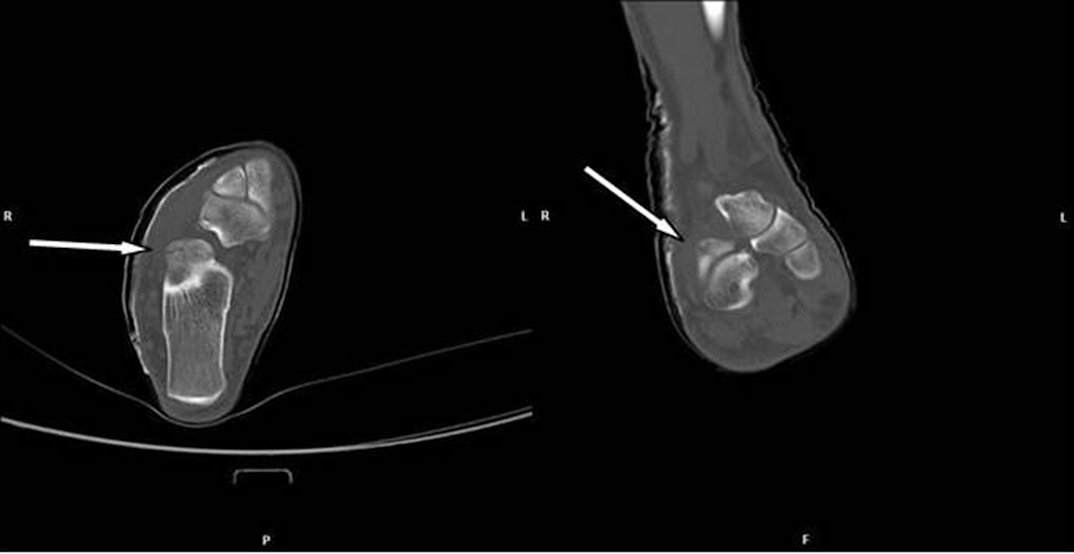

Figure 3: Scan of the calcaneus with a discrete fracture without dislocation of the bone: CT taken at the initial examination. Arrays indicate the fracture lines

Six weeks later, the patient received a control examination for the healing process. To reduce radiation dose, a CBCT was performed. A thin fracture line of the calcaneus was clearly visible (Figure 4 [Fig. 4]). Some sections indicated ossification signs as proof of a healing process (Figure 4 [Fig. 4]). Hence, there was no need for a surgical approach.

Figure 4: Scans of the calcaneus with a discrete fracture without dislocation of the bone: CBCT taken 6 weeks later at a follow-up examination

CBCT easily detected a discrete fracture in the complex calcaneus. Comparing with CT, the thin fracture was more distinct in the CBCT scans although the fracture was readily in healing process and therefore should be less visible. Consequently, an even distinct imaging of the fracture could be expected by a CBCT scan at initial diagnosis.